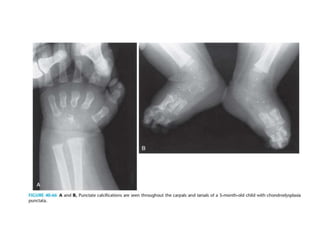

• Hallmark of the disease is the presence of multiple punctate

opacities(non specific) in the unossified cartilage at the ends

of the long bones, the tarsals, the pelvis, and the vertebrae.

• Early diagnosis is important because the characteristic

punctate calcifications disappear within the first year of life